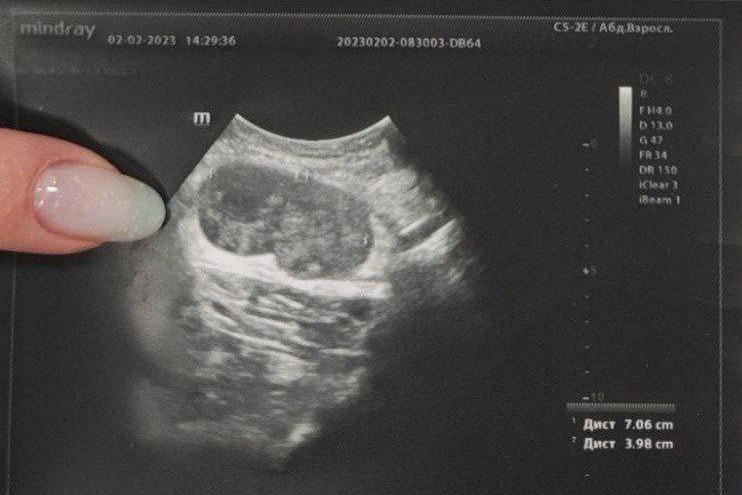

«Пациент обратился к нам с жалобами на «шарик» подмышкой. При ультразвуковом исследовании было установлено, что это увеличенный лимфоузел размером 70/40 миллиметров с изменённой структурой. Находка вызвала подозрения, пациента направили на дополнительное обследование — выполнение биопсии лимфоузла для установления точного диагноза», — рассказала врач ультразвуковой диагностики ЦГКБ №3 Жанна Краснопёрова.

ФОТО: ТГ «Здоровье уральцев».